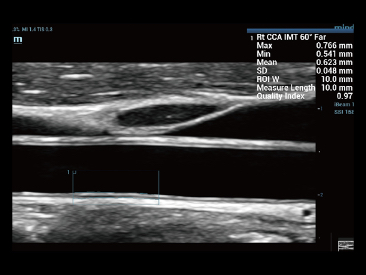

Fin dalla sua fondazione Mindray esplora continuamente nuovi modi per migliorare l'affidabilit├Ā diagnostica. Equipaggiata con la pi├╣ rivoluzionaria tecnologia ZONE Sonography?, la nuova piattaforma ZST+ di Resona 7 porta la qualit├Ā dell'immagine ecografica ad un livello superiore con l'acquisizione per zone e l'elaborazione dei dati canale.

Oltre alla qualit├Ā delle immagini di livello eccellente, Resona 7 migliora anche le capacit├Ā di ricerca clinica il rivoluzionario V Flow per la valutazione emodinamica vascolare, e l'acquisizione piani pi├╣ intelligente dal set di dati 3D per la diagnosi del sistema nervoso centrale fetale. Combinando il pi├╣ intuitivo funzionamento multi-touch basato su gesti e tutte le caratteristiche cliniche essenziali, Resona 7 sta veramente portando nuove tendenze nellŌĆÖinnovazione dellŌĆÖecografia.